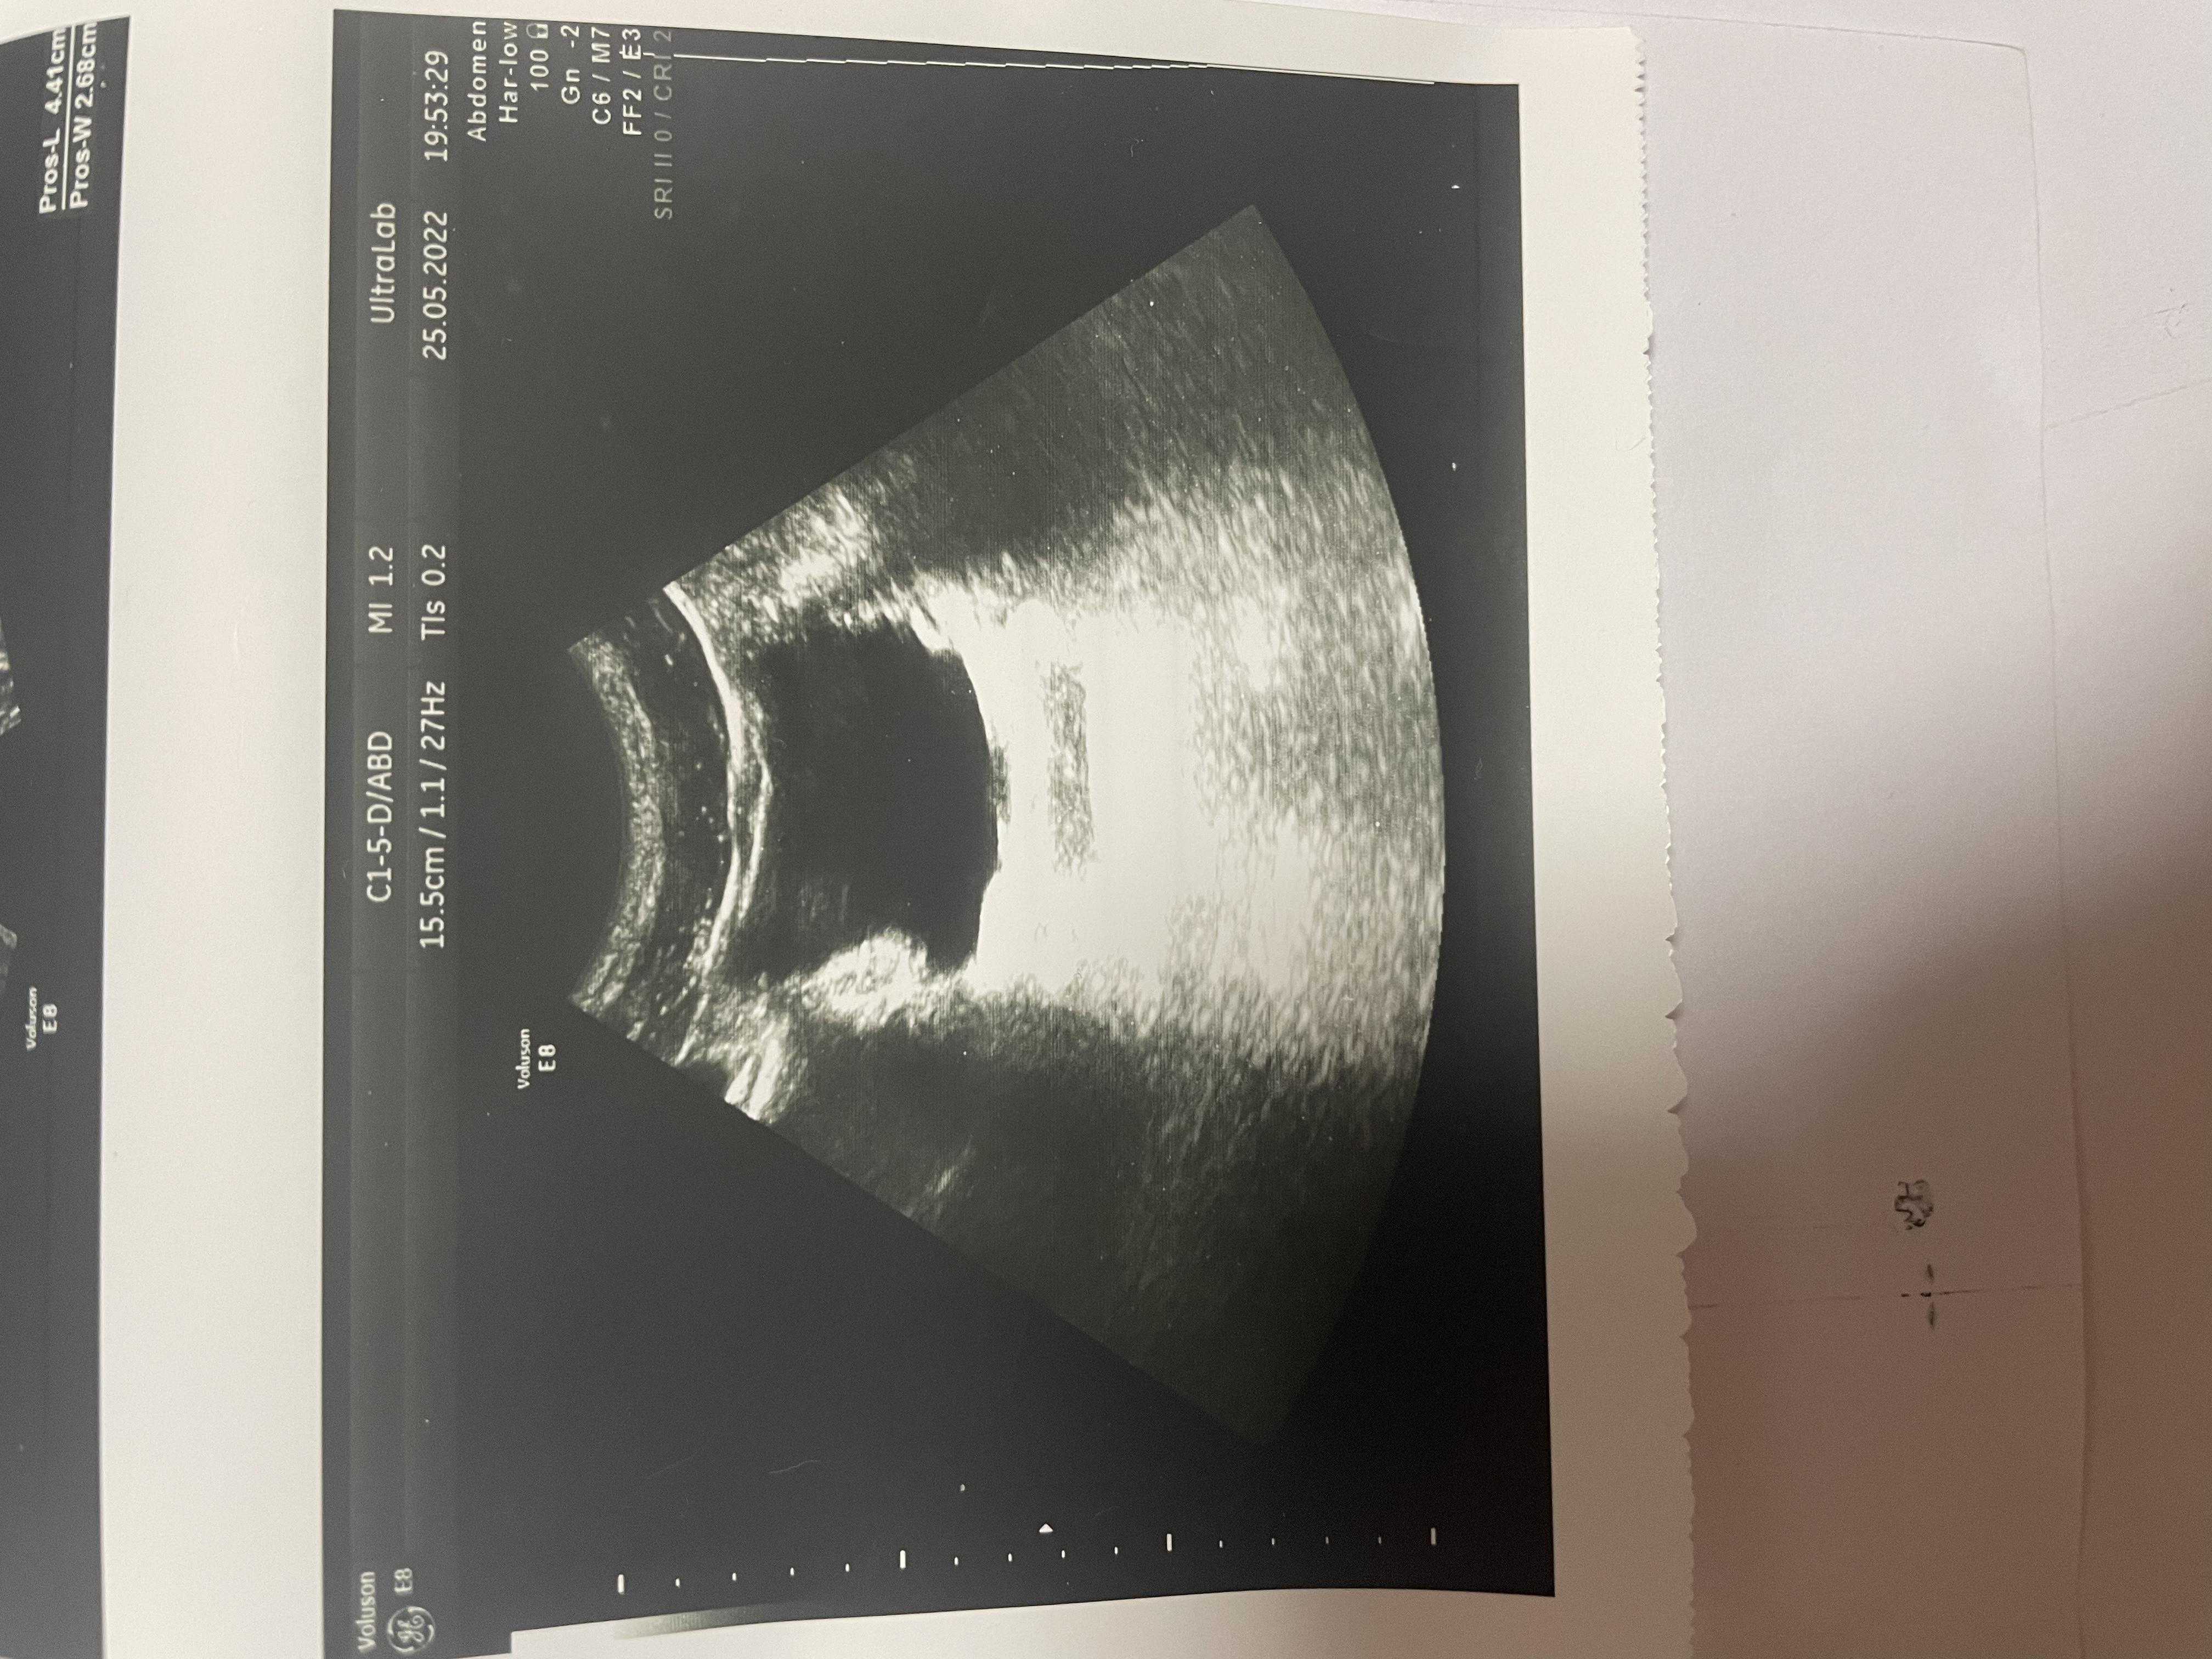

Здравствуйте, болят яички 1.5 года. 6 месяцев режет при мочеиспускании, боли в копчике (начинается с копчика, в течение дня усиливаются, поднимаются выше боли). Может ли это быть из-за мочевого пузыря? Фото прикрепил, там есть образование некое. Бак посев мочи отриц, эр, лейк. в норме, зппп отриц, в секрете простаты клебсиела, кровь в норме, млча в норма. Мрт поясницы делал, невролог сказал, что боли точно не из-за невролгии.

Добрый день! Вам нужно выполнить МРТ малого таза - там будет видно образование в стенке мочевого пузыря (если оно действительно есть). После этого надо обратиться к онкоурологу для интерпретации результатов МРТ и решения вопроса о дальнейшей тактике. Удачи.